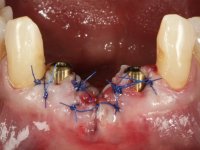

After an imaging study, the placement of two implants of 3.3 mm in diameter and 10 mm in length was planned. On the day of surgery, teeth 42 and 32 were extracted and the implant was removed. The implants were placed in the area of the alveoli, taking care to slightly lingualize their positioning. An impression was made using the open tray technique with the flap open for the fabrication of the immediate provisional bridge. While the impression was taken to the laboratory, tall healing screws were placed and the surgical wound was sutured. The patient waited 2 hours in the waiting room while the temporary bridge was made in the laboratory. An immediate screw-retained provisional bridge was placed and its seating was controlled by imaging. After 3 months, the final impression was made using an open tray technique. In this consultation, we took the opportunity to polish the temporary bridge with rubber cups so that the soft tissues could mature in better conditions. Information was collected to better characterize the monolithic structure in Zr. Color guides were used for the coronal and gingival ceramics. In the laboratory, a bridge was made in Zr. bolt-on that has been carefully characterized. After approval by the patient, it was definitively placed in the mouth. Tightening was performed with a dynamic wrench with a torque of 35 N. The holes were covered with Teflon and filled with composite resin.